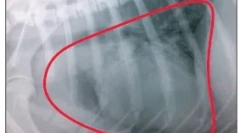

Scanarea cu ultrasunete sau modelul de difracție cu raze X vă permite să obțineți o analiză a tumorilor sanguine și se efectuează analiza urinei pentru a evalua starea acestuia.